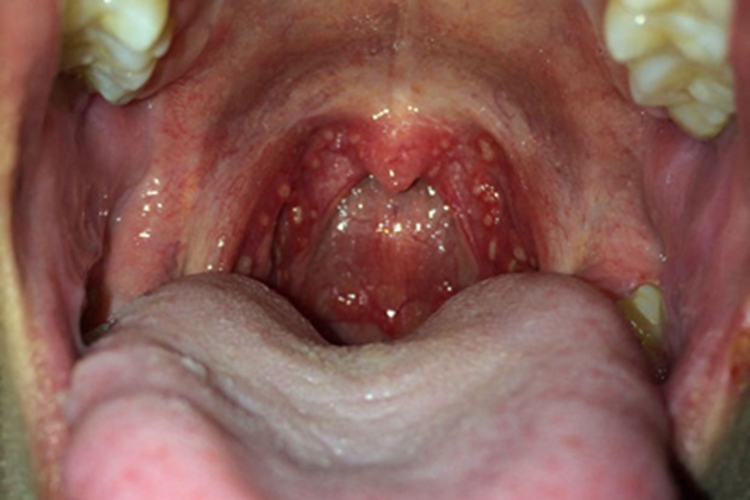

化脓性扁桃体炎检查可见患者的扁桃体化脓,表面有黄白色小脓点,同时可伴有高热、全身不适等症状,常由溶血性链球菌感染引起。

化脓性扁桃体炎常导致患者的扁桃体受累,引起化脓,检查可见表面有黄白色小脓点,或有黄色脓性分泌物,其脓性分泌物可连接成片,呈伪膜状,边界清晰,易擦去。同时患者还可伴有咽痛吞咽时加重、高热、全身不适等症状。